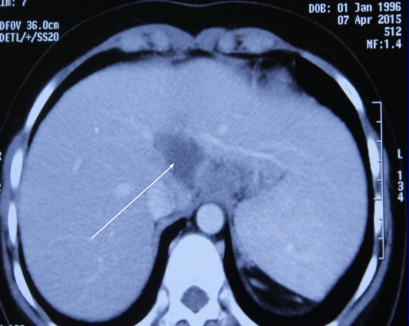

Lao gan là bệnh lý hiếm gặp, khó chẩn đoán và dễ nhầm lẫn.

Theo các chuyên gia y tế, lao gan là bệnh hiếm gặp, y văn thế giới mới ghi nhận 2 ca. Ca bệnh đầu tiên ở nước ta vừa được các bác sĩ Bệnh viện Chợ Rẫy (TP.HCM) chữa khỏi.